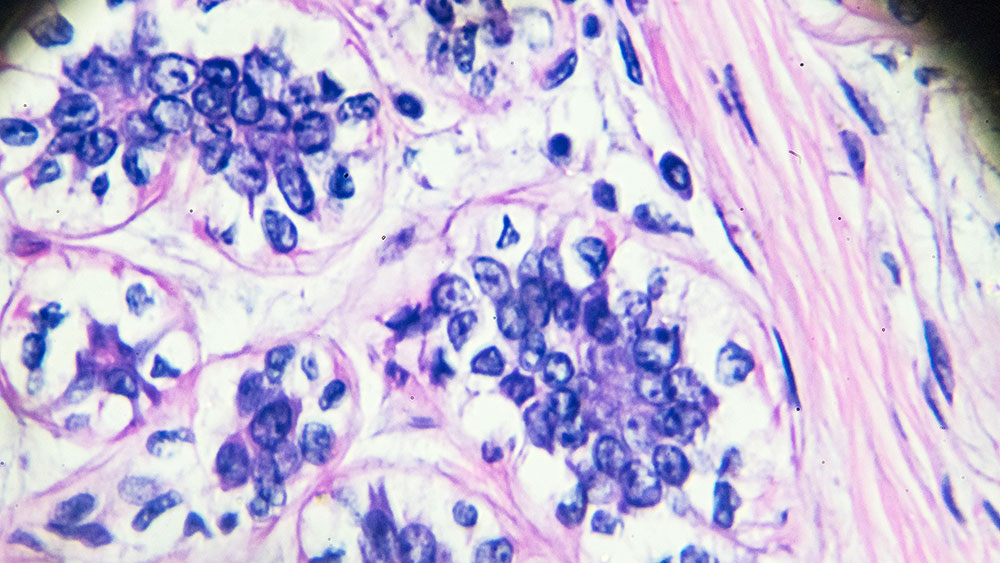

Breast cancer under light microscopy

沈博士杨是一个随着文章的第二作者ch study that has identified a protein that drives breast cancer stemness and metastasis. This research is led by Dr. Huiping Liu with the Northwestern University Feinberg School of Medicine.